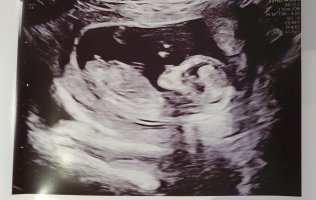

Dette er en tydelig jente! Ultralyd er jo snitt av kroppen, det betyr at ikke alt er synlig samtidig og da kan jo f.eks deler navlestreng eller lårbein eller en hånd som stikker ned se ut som noe er mellom beina litt her og der. Hvis du er 14 uker så hadde du sett en ganske tydelig penis nå. Hos gutter ser man gjerne at blæren er mye lavere hvis penis ikke skulle blitt med på bilde.Mulig å se noe her? Syntes jeg så en tydelig snopp på ultralyden, men jordmoren sa hun holdt en finger på jenteMålt til 14+0

Ser ut som en jente

Dette må være en jente. Nub har ikke antydning til vinkel en gang.

Var på ul i dag.ÅååDette er en tydelig jente! Ultralyd er jo snitt av kroppen, det betyr at ikke alt er synlig samtidig og da kan jo f.eks deler navlestreng eller lårbein eller en hånd som stikker ned se ut som noe er mellom beina litt her og der. Hvis du er 14 uker så hadde du sett en ganske tydelig penis nå. Hos gutter ser man gjerne at blæren er mye lavere hvis penis ikke skulle blitt med på bilde.

Er ikke ofte man ser et så bra bilde av nub, Så her ser man kjønnet godt og det er ingen tvil.

På bildet jeg legger ved ser du tydelig de to strekene på jente, mens en gutt i uke 13 ville stått opp med stacking.